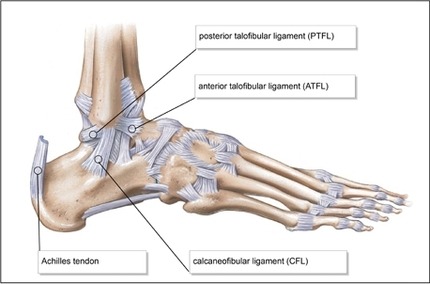

5. 외측측부인대를 형성하는 세 인대의 이름을 대시오.

외측측부인대를 구성하는 세 인대는 전거비인대(anterior talofibular ligament), 종비인대(calcaneofibular ligament), 후거비인대(posterior talofibular ligament)이다.

△ 발목외측인대 (이미지 출처 : http://ankl.weebly.com/diagram.html)

6. 외측측부인대를 형성하는 세 인대 중 어느 인대가 먼저 파열되는 경향이 있는가?

전거비인대(anterior talofibular ligament)가 가장 흔하게 손상받는 인대이다. 종비인대(calcaneofibular ligament)는 다음으로 흔하게 손상받는 인대이다. 후거비인대(posterior talofibular ligament)는 관상면 MRI 영상에서 쉽게 확인되지만 손상이 드물다.